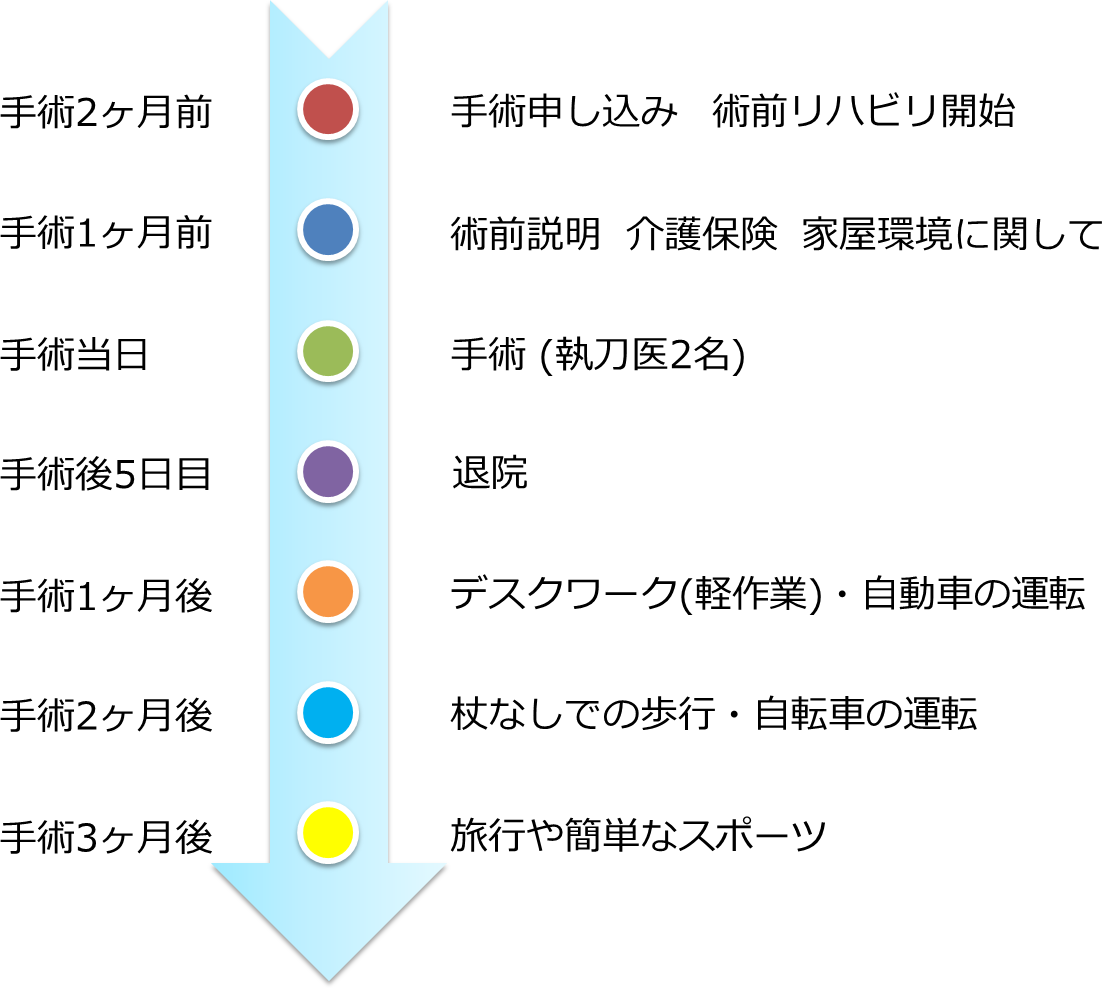

手術前から社会復帰までの流れは?

手術を申し込まれてから約1-2か月間の手術前リハビリを実施しています。

また手術までの間にソーシャルワーカーによる手術前説明を行います。

入院は手術当日です。

術後のリハビリは1日2回行い、5泊6日での退院となります。

退院後は執刀医による定期的な診察や外来リハビリ(週1-2回)を行います。